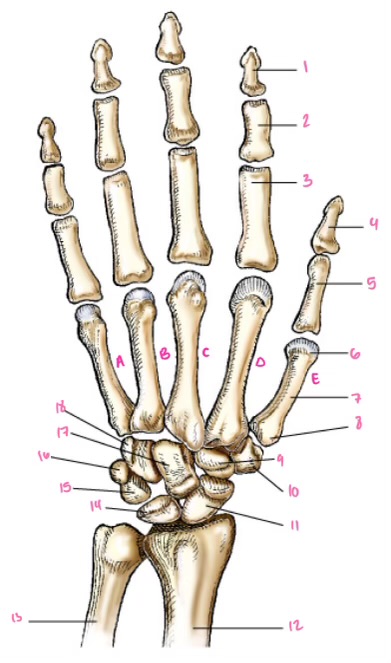

1

Distal interphalangeal

13

2

Proximal Interphalangeal

14

3

Metacarpophalangeal

15

4

Intercapals

16

5

Distal radioulnar

17

6

Radiocarpal

18

7

Carpometacarpals

19

8

Metacarpophalangeal

20

9

Interphalangeal

21

7

Trapezoid

22

8

Trapzium

23

9

Capitate

24

10

Scaphoid

25

11

Lunate

26

13

Carpus

27

14

Triquetrul

28

15

Hamate

29

16

Metacarpus

30

17

Phalanxes